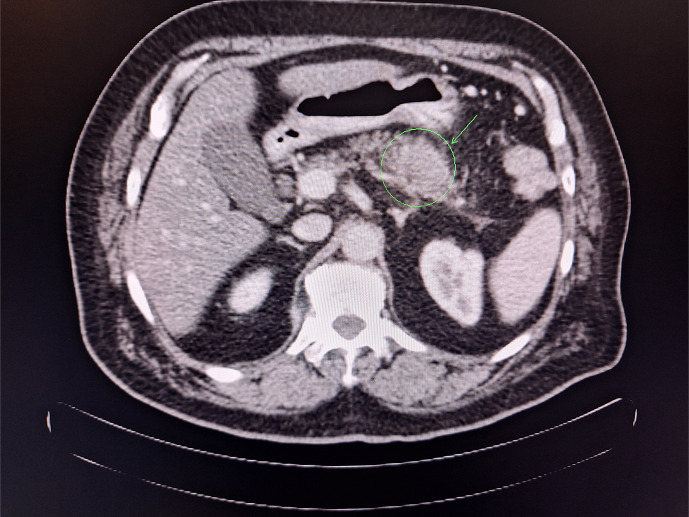

Case presentation: A 70-year-old male presented with weight loss and abdominal pain in July 2018, was diagnosed with stage IB PDAC (pT2, pN0, M0), and underwent successful R0 resection. Adjuvant chemotherapy with FOLFIRINOX (5-FU, LV, irinotecan, and oxaliplatin) was given for 9 cycles between September 2018 and January 2019, and the patient remained recurrence-free until a computed tomography scan revealed soft tissue mesenteric infiltrations in July 2020. First-line palliative chemotherapy with nab-paclitaxel + gemcitabine was initiated and continued until January 2022 when disease progression in the form of two metastatic hepatic lesions was observed. Second-line palliative chemotherapy with nal-IRI 129 mg on day 1 + capecitabine (CAP) 4,000 mg daily for the first 7 days of each 14-day cycle was initiated (due to previous 5-FU intolerance). Response (reduced oncomarkers) was observed, and treatment with nal-IRI + CAP continued, with liver-directed treatment in September 2023, until February 2024. During second-line therapy, side effects (mild diarrhoea) were infrequent and manageable.

Abstract Image